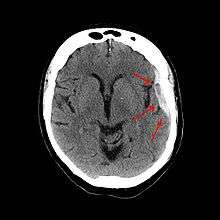

| Subdural hematoma as marked by the arrow with significant midline shift | |

On a CT scan, subdural hematomas are classically crescent-shaped, with a concave surface away from the skull. However, they can have a convex appearance, especially in the early stage of bleeding. This may cause difficulty in distinguishing between subdural and epidural hemorrhages. A more reliable indicator of subdural hemorrhage is its involvement of a larger portion of the cerebral hemisphere since it can cross suture lines, unlike an epidural hemorrhage. Subdural blood can also be seen as a layering density along the tentorium cerebelli. This can be a chronic, stable process, since the feeding system is low-pressure. In such cases, subtle signs of bleeding such as effacement of sulci or medial displacement of the junction between gray matter and white matter may be apparent. A chronic bleed can be the same density as brain tissue (called isodense to brain), meaning that it will show up on CT scan as the same shade as brain tissue, potentially obscuring the finding.